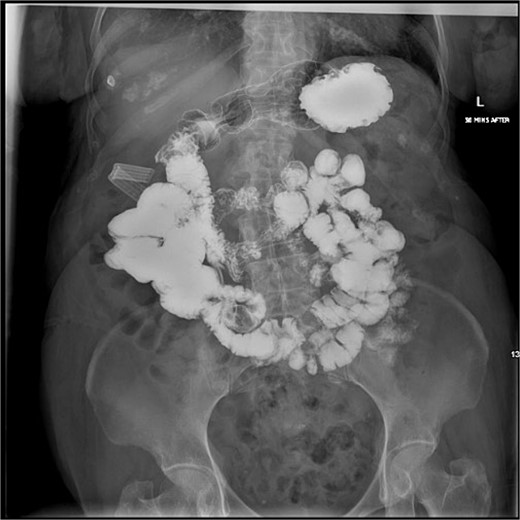

She underwent a diagnostic laparoscopy revealing a transition point secondary to the impacting 3-cm gallstone in the mid-jejunum. A small laparotomy was used to perform an enterotomy, stone extraction, and enterotomy closure. She had an unremarkable postoperative course. After 2 months, a follow-up CT revealed pneumobilia and a likely cholecystoduodenal fistula (Fig. 2). After medical optimization, she was scheduled for an elective robotic cholecystectomy and repair of the fistula 7 months later.

CT scan from follow-up after the index procedure. A) Axial CT: cholecystoduodenal fistula; air-filled gallbladder (superior, green arrow), duodenum (inferior, white arrow), B) Axial CT: air-filled gallbladder (superior, green arrow), duodenum (inferior, white arrow), C) Coronal CT: cholecystoduodenal fistula; air-filled gallbladder (superior,green arrow), duodenum (inferior, white arrow), D) Coronal CT: air-filled gallbladder (superior, green arrow), duodenum (inferior, white arrow).